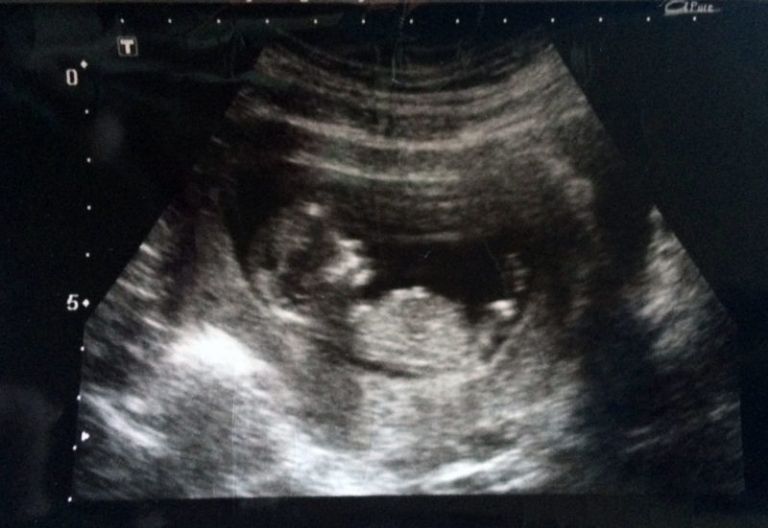

图为萨默肚子里的孩子,已经有三个月大。